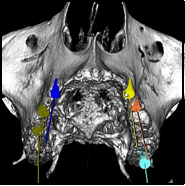

Il termine più corretto è chirurgia computer assistita perchè il computer non guida il chirurgo orale ma è quest’ultimo che, attraverso l’utilizzo di un software di elaborazione 3D, viene aiutato nella programmazione di chirurgie implantari e/o ricostruzioni ossee ed estrazioni particolarmente complesse. Dopo aver eseguito una TC (tomografia computerizzata, la vecchia tac) dell’arcata dentaria interessata, i dati ottenuti vengono elaborati per ottenere un modello virtuale tridimensionale su cui il chirurgo programma, con grande precisione, l’intervento che eseguirà sul paziente. Questa tecnologia permette di visualizzare assieme al paziente il risultato finale ancor prima di eseguire la chirurgia; di programmare nel dettaglio numero e posizione degli impianti consentendo di stabilire se sarà possibile consegnare un provvisorio  fisso al paziente nell’arco di 24-48 ore; di eseguire, nei casi favorevoli, interventi senza incisioni annullando o riducendo così i sintomi postoperatori che accompagnano la chirurgia convenzionale; di intervenire in sicurezza su pazienti con patologie sistemiche e/o in terapia farmacologica grazie alla riduzione dell’invasività e quindi del sanguinamento; di visualizzare le strutture anatomiche nobili (vasi sanguigni e nervi) presenti nei mascellari e quindi condurre l’intervento in grande sicurezza. Infine, ma non meno importante, di ridurre il tempo della seduta chirurgica alla poltrona.